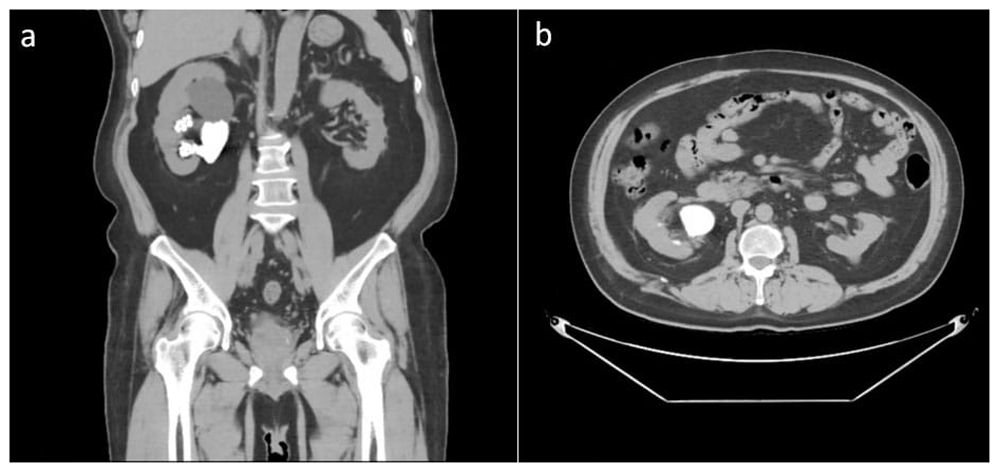

Computed tomography (CT) urography at the previous hospital showed a staghorn stone at the right inferior calyx with a size of 45.7 × 59.3 × 27.5 mm (Hounsfield unit not available), a left renal cyst with size of 19.2 × 22.2 × 18.9 mm, and a third-grade right-side hydronephrosis (Figure 1). Post-RIRS photo showed a double J stent with multiple tiny stones from the right pelvio-calyces to vesico-ureteral junction (Figure 2a).

The first CT Urography of the patient shows right staghorn stone with grade 3 hydronephrosis and left renal cyst.